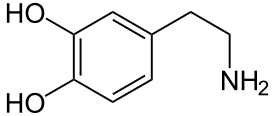

Im Endothel der Blut-Hirn-Schranke sind mehrere Transportsysteme, um das Gehirn mit essentiellen hydrophilen Substanzen zu versorgen. Ein Ansatz, Wirkstoffe in das Gehirn schleusen zu können, ist die Ausnutzung dieser Transporter. Dies wird beispielsweise bei der Therapie der Parkinson-Krankheit angewendet. Daran erkrankte Patienten haben im Gehirn einen Mangel des Neurotransmitters Dopamin. Die Gabe von Dopamin wäre diesbezüglich wirkungslos, da Dopamin die Blut-Hirn-Schranke nicht passieren kann. Verabreicht man dagegen Levodopa, eine nicht-proteinogene α-Aminosäure, so wird diese über den LAT1-Transporter dem Gehirn zugeführt und dort anschließend in Dopamin verstoffwechselt. Der LAT1-Transporter gehört zur Familie der LNAA-Transporter (large neutral amino acid).[37]